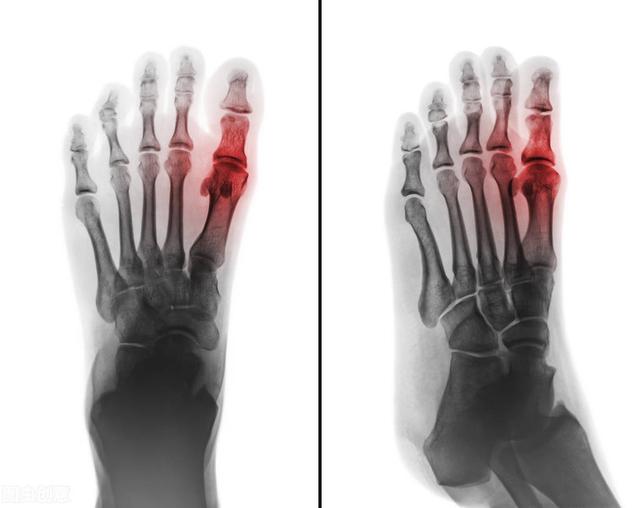

尿酸高容易诱发痛风、结石、关节炎这是大家的一个共识了,但中医是怎样看待这事的呢?

中医认为,痛风也好,结石也好,下肢关节炎也好,主要成因是因为——湿热。

主要是因为我们的饮食结构跟古时候发生了非常大的改变,以前作为平民百姓,饥不果腹,只有皇宫大臣才会像我们现在那样大口吃肉,想吃多少就吃多少。当肉类摄入过多。不能有效地运转消化之后,湿浊就在身体里面堆积,加之现代人久坐不运动,脾胃运化差,消耗过多营养的能力变差了。加上近1-2年流行起来的吃辛辣的火锅,辛辣的小龙虾,辛辣的烧烤,奶茶当水喝,久坐不运动导致这些湿和热,胶着在一起。形成我们所说的湿热症。病情轻则就是痔疮、皮肤起疙瘩,脂肪瘤。病情严重的就出现结晶。导致痛风结石。当结晶体积攒在关节处,就形成了我们的湿热性关节炎。